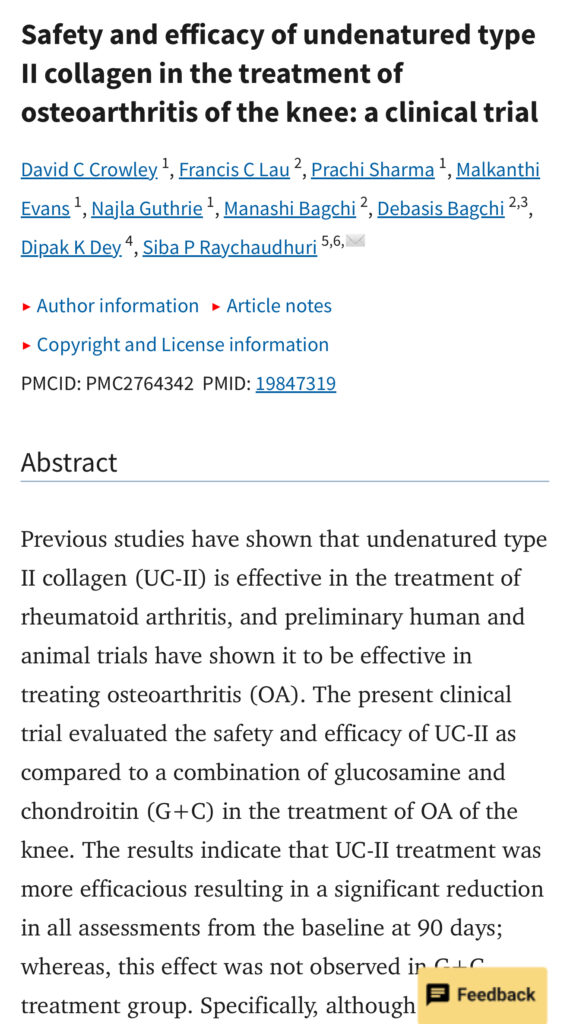

A patented Type II Collagen, sourced from chicken cartilage from USA.

- Rebuild and reduce cartilage & Joint Fluid Loss

- Relieve Pain & Restores joint flexibility

- Proven to be 2x more effective than glucosamine + chondroitin